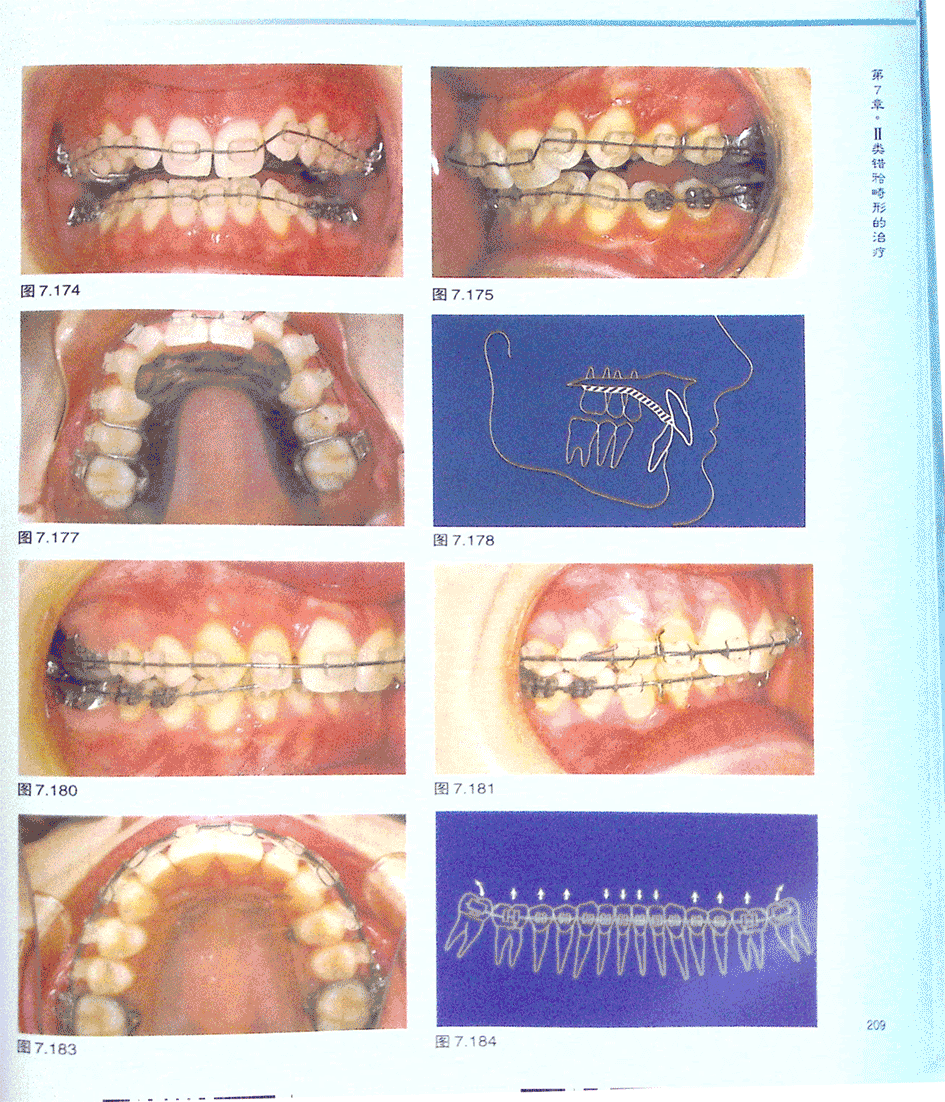

病例DO:成人Ⅱ类2分类拔除磨牙治疗(二)